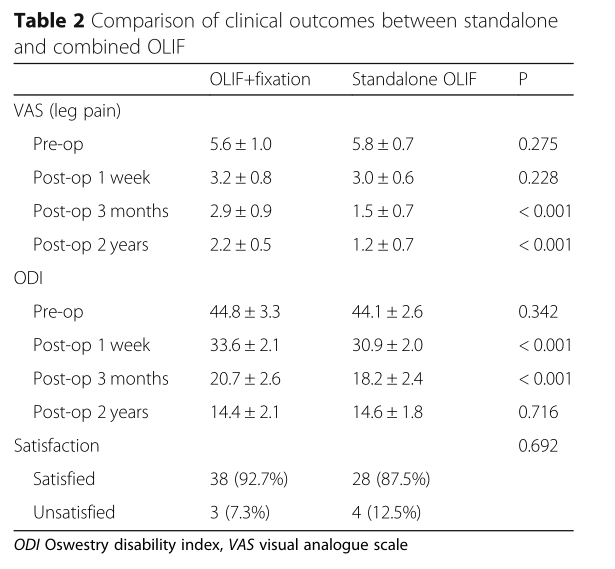

随访2年,VAS和ODI评分无差异,但独立OLIF在1周和3个月时评分更好(P <0.05)。与独立的OLIF组相比,手术前和手术后OLIF组的PDH和FW较小(all P <0.05)。两组之间在术前,第1周和第3个月时的FH有显着差异(all P <0.05),但在第2年时差异消失(P =0.111)。

OLIF联合治疗组分别在3个月和24个月时发生cage下陷,分别为7.3%(3/41)和7.3%(3/41),而6.3%(2/32)和15.6%(5 / 32)分别在独立的OLIF组中的相同时间点显示(P = 0.287)。两组在2年时均没有退笼。3个月时,联合OLIF组的融合率为85.4%(35/41),而独立OLIF组的融合率为84.4%(27/32)(P = 0.669)。在24个月时,联合OLIF组的融合率为100.0%,而独立OLIF组的融合率为93.8%(30/32)(P = 0.066)。